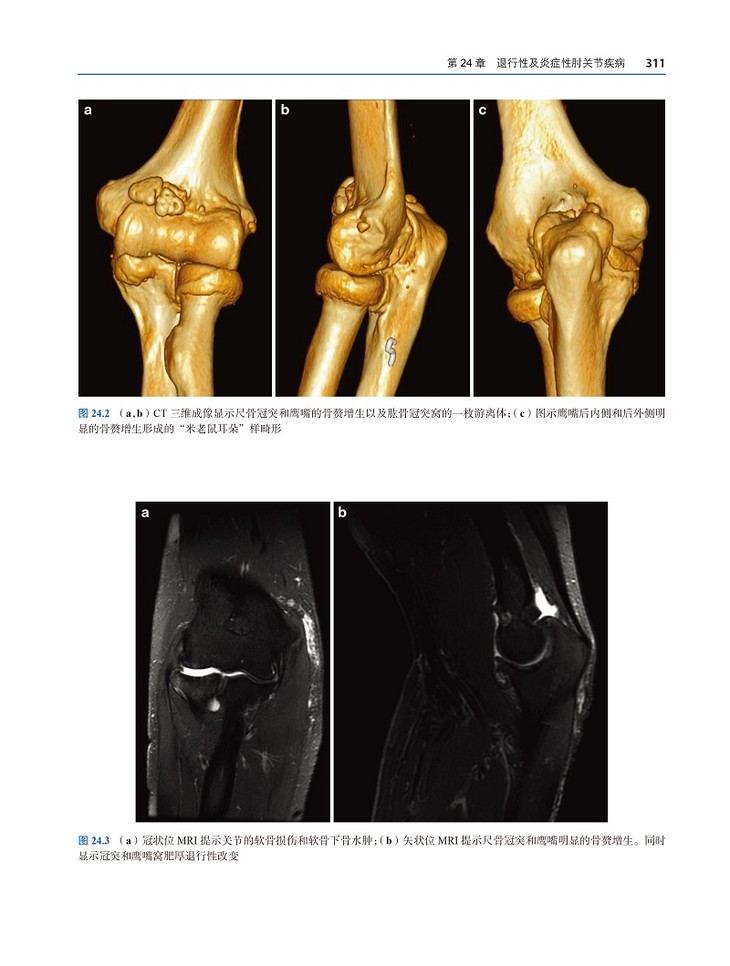

书名:关节磁共振成像与关节镜图谱